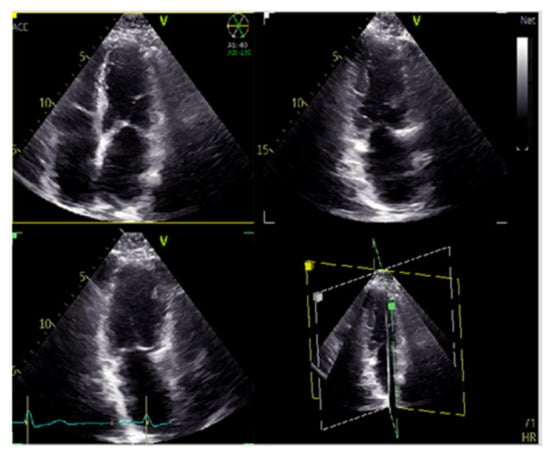

7. Fusion Imaging

The evaluation of cardiac function in real-time with increased spatial resolution has become critically important during transcatheter interventions and is gaining ground day by day as a mainstay in cardiac care with regard to treatments for structural heart disease. These procedures, while minimally invasive for patients, often have added degrees of patient-related and procedure-related complexity. Fluoroscopy has long been the cornerstone of interventional procedures due to the excellent device visualization and due to the fact that it provides real-time feedback. On the contrary, fluoroscopy offers poor characterization of non-radiopaque structures and provides only 2-D projections of important 3-D cardiac anatomy, lacking essential spatial resolution. Fusion imaging combines data from different imaging modalities, fluoroscopy, computed tomography, and echocardiography, in order to produce a fused image, video, or live streaming (Figure 14). With these methods, we have access to high-resolution detailed anatomic information from CT imaging combined with functional, real-time motion and flux information from echocardiography. The fusion of the pre-operative CT and the peri-procedural 4D-TEE provides us with an excellent visualization of both images in the same visual perspective on the echo screen in the catheterization laboratory [38,39,40,41,42].

Figure 14. CT Fusion image the display of co-aligned 4D TEE ultrasound and CT data.